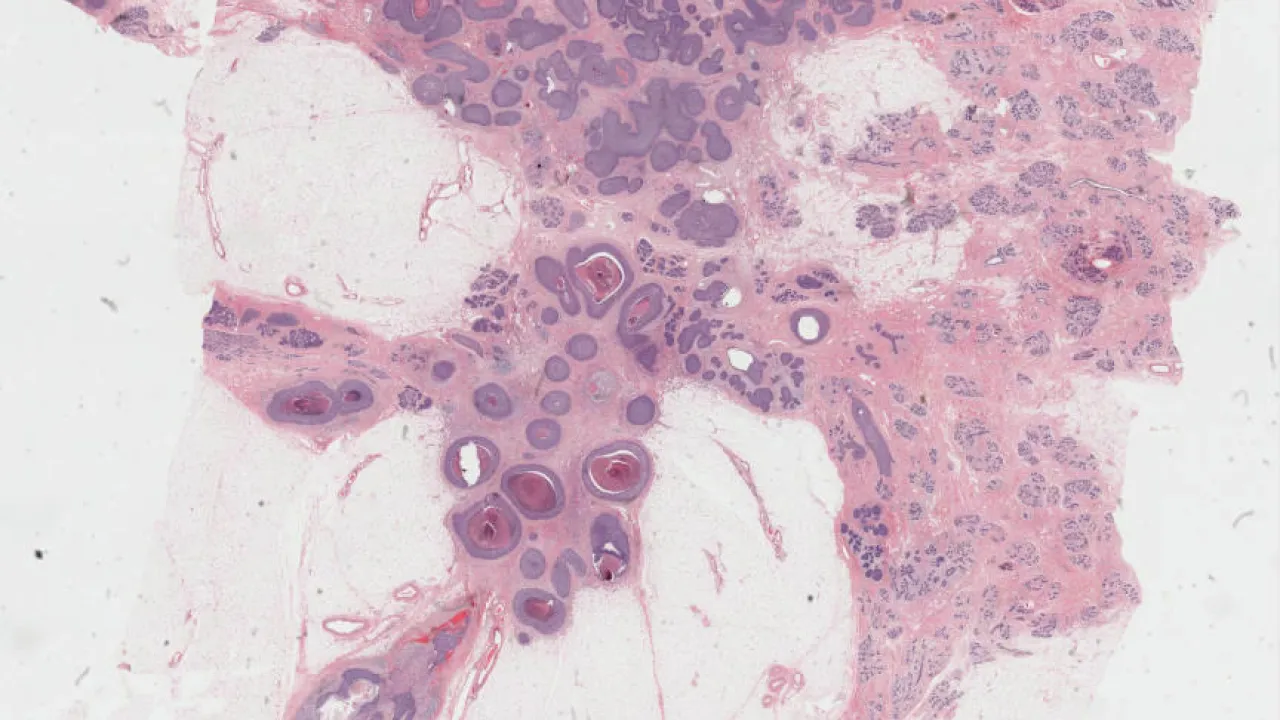

Skin, Involuting infantile hemangioma, H&E stain